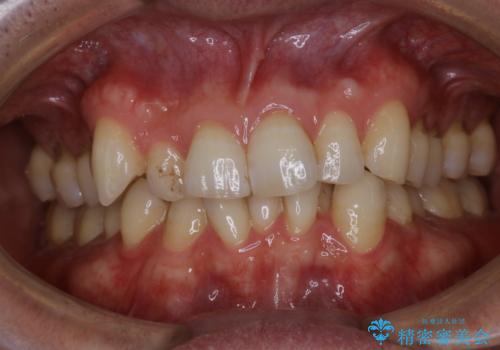

1日で着色を除去し綺麗な歯に

- 前歯の汚れが気になるため、綺麗にしたいとのことで来院されました。PMTC30分コースを行いました。

毎日丁寧に歯磨きをしていても、日常生活での飲食物などにより着色してしまうことはあります。PMTCでは、歯の表面の凸凹にミネラルを補給して、ツルツルの表面に仕上げます。定期的にPMTCを行うことにより、歯質の強化になり着色がつきにくい状態になります。